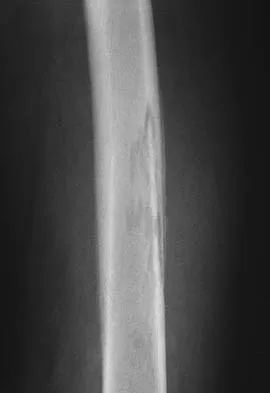

Figures 12a and 12b show the radiographs of a 50-year-old patient who reports acute knee pain after sustaining a twisting injury while playing tennis. Examination is unremarkable. The next most appropriate step in management should consist of

Explanation

The radiographs show localized diffuse cortical thickening that is characteristic of melorheostosis. The condition may be monostotic or it may involve many bones in one extremity (monomelic) in the distribution of a sclerotome. Bone scans will show increased uptake at the site or sites of skeletal involvement. Long tubular bones are most commonly involved. Melorheostosis is usually asymptomatic and requires no treatment. On rare occasions, there may be associated soft-tissue contractures. Dorfman H, Czerniak B: Bone Tumors. St Louis, MO, Mosby Inc, 1998, pp 1105-1107. Campbell CJ, Papademetriou T, Bonfiglio M: Melorheostosis: A report of the clinical, roentgenographic, and pathological findings in fourteen cases. J Bone Joint Surg Am 1968;50:1281-1304.